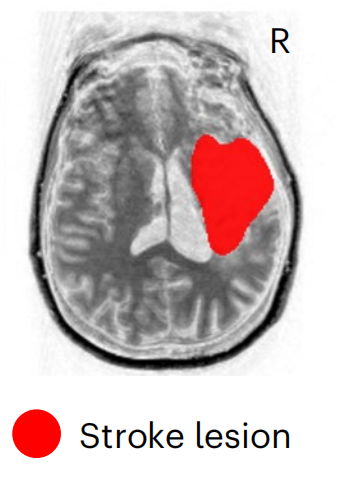

病例1:女,31岁,在参与该研究的九年前,因海绵状畸形继发于右侧丘脑出血性中风,病变局限于内囊、中脑和脑桥,FAS=0.17,Fugl-Meyer运动评估显示中度损伤。 病例2:女,47岁,在参与本研究的三年前,因右颈动脉夹层导致右侧缺血性大脑中动脉(MCA)卒中,导致大面积MCA梗死。SCS01的,病变范围较大,影响右半球的放射冠,FAS=0.35,Fugl-Meyer运动评估显示重度损伤。 SCS01 SCS02 治疗方案